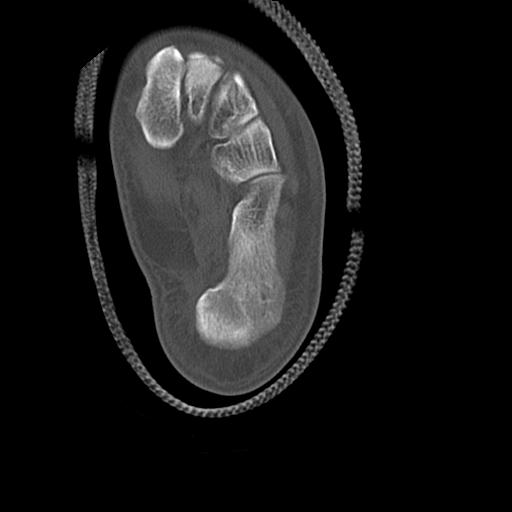

102755 1/4 2R 1/15 2R 右足関節 68歳女性 右三果脱臼骨折

56476 8/28 4R 1/21 2R 左足関節 デジカメ写真 72歳女性 右足関節AS